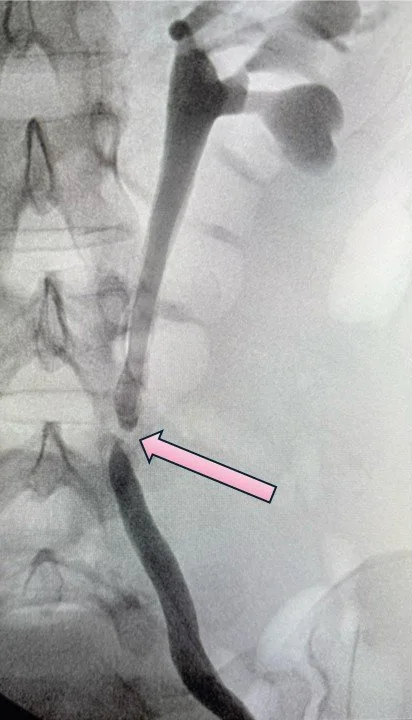

The image on the left is an x-ray of a patient sent to me with an injured ureter. The ureter is the long thin tube, but the bottom section of the doesn’t make it all the way down to the bladder, the round structure on the bottom left. There is a bad scar that formed - a stricture - that completely obliterated the ureter tube hollow center, so no urine could drain. This is called a "distal" stricture because it is the bottom of the ureter, closest to the bladder and furthest from the kidney. I performed a robotic ureteral reimplant with a Boari flap (image on the right) and fixed the problem. A Boari flap is a procedure where you use part of the bladder wall to make a new connection up to the ureter.

BOARI FLAP CONNECTNG URETER BACK TO BLADDER